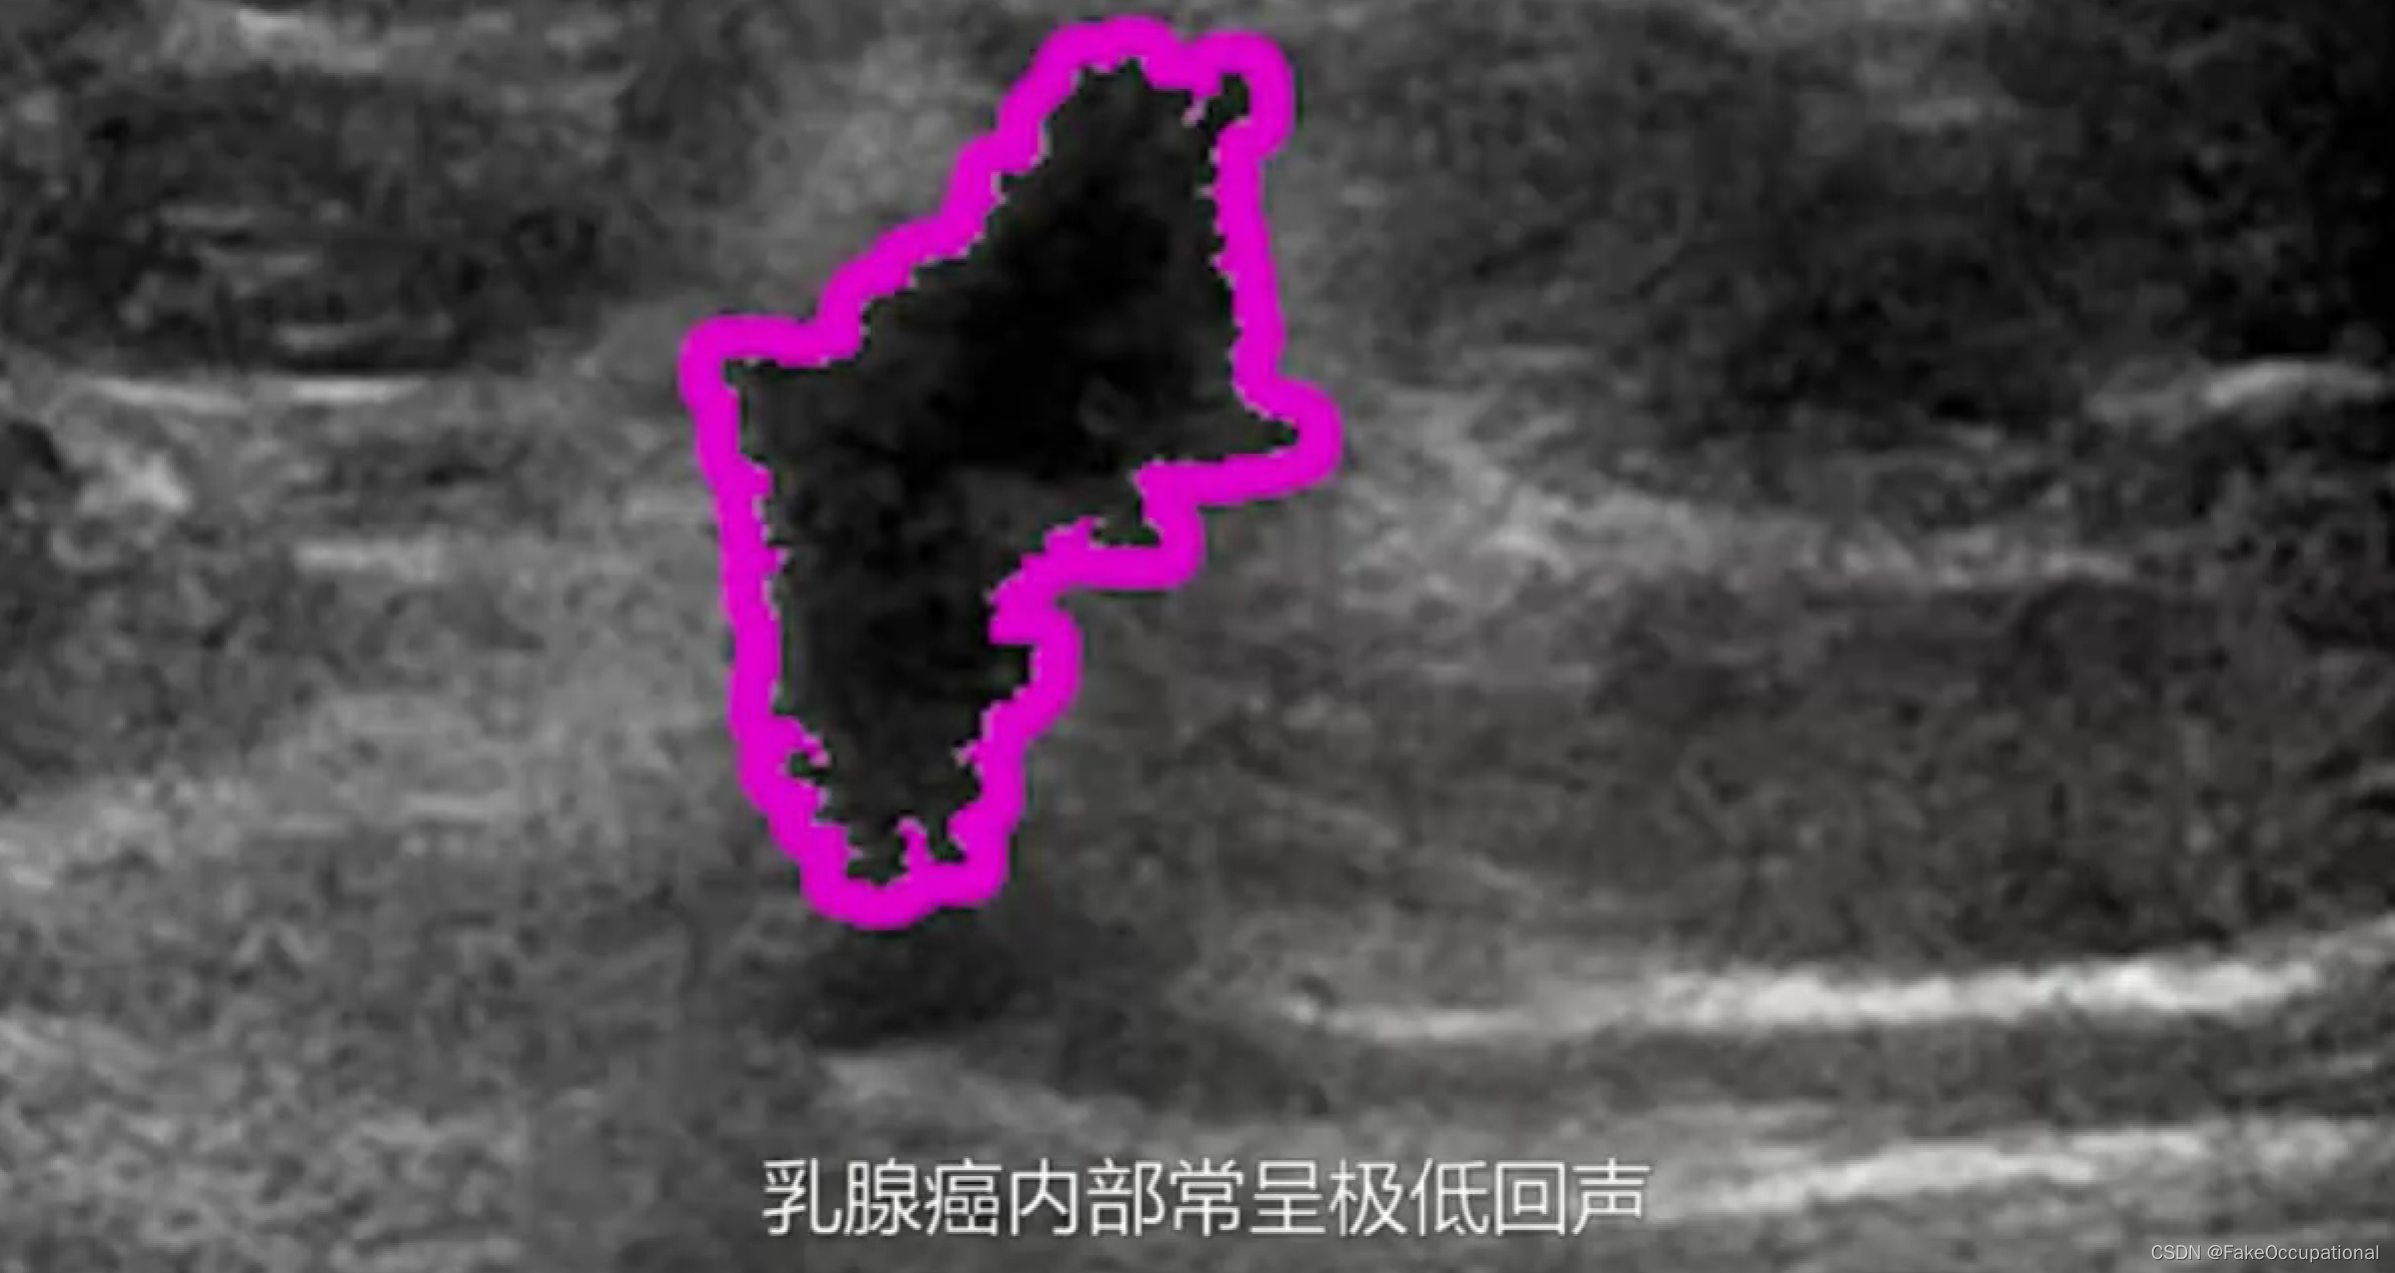

乳腺癌

- 患者18岁,微小癌

- 其理论依据是恶性肿瘤常星离心性生长

- 淋巴结转移